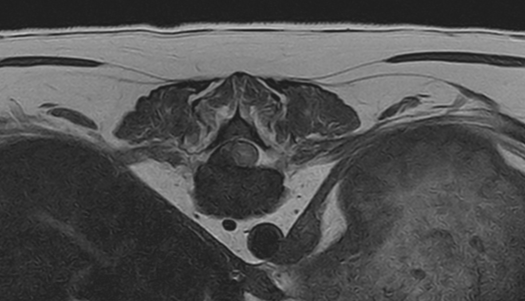

02척추 MRI

· 통증, 마비의 원인 진단

· 척추 실질 질환의 진단

· 추간판 탈출증, 척수공동증, 척수연화증 등

3T MRI

기존 본원에서 이용하던 1.5T 장비와 비교하여 높은 해상도와 빠른 스캔 시간(촬영 부위 당 30분 미만)으로 MR 촬영 시 환자의 마취 부담을 줄일 수 있습니다.

3T MRI는 국내 동물병원에서 최상급 촬영 장비에 해당하며 본동물의료센터의 MRI는 3T MRI 중에서도 하이엔드급 장비(Philips Ingenia)를 사용하고 있습니다.